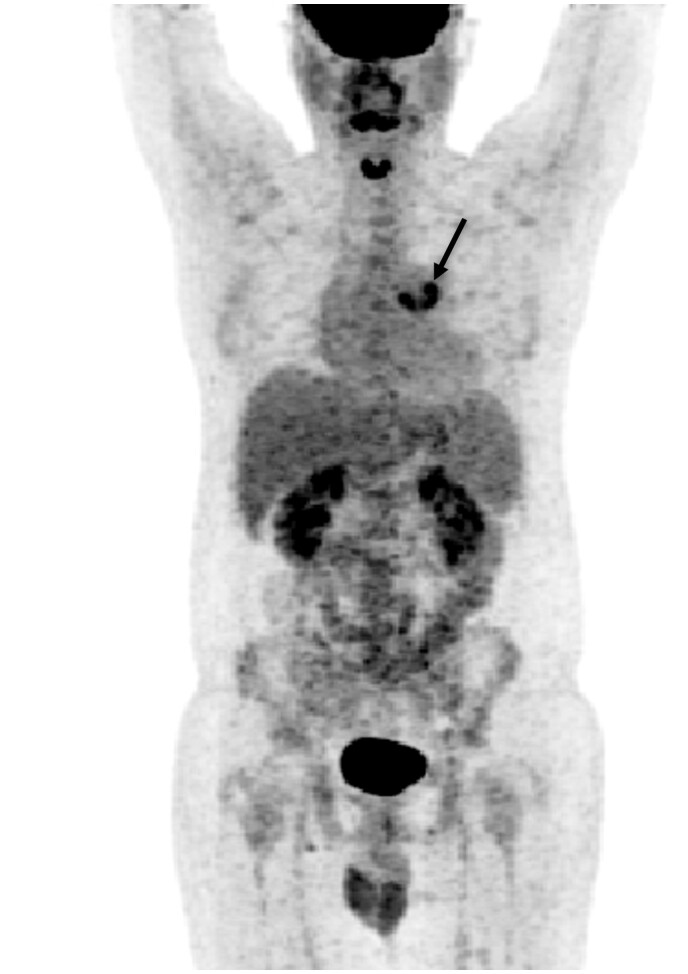

Q fever is an epidemic disease caused by the Coxiella burnetii infection. It can manifest clinically as an acute or chronic disease, with chronic infections being more common. Q fever endocarditis is the most common manifestation of chronic infection and usually occurs in patients with previous valvular heart disease like in our present study, a case of Q fever endocarditis that occurred in background of tetralogy of Fallot surgical repair. However, Q fever endocarditis is difficult to diagnose clinically and may lead to very serious or even life-threatening outcomes if not diagnosed promptly. In the present study, accurate diagnosis and treatment were achieved by 18F-FDG PET/CT combined with detection of the Q fever serological antibodies.